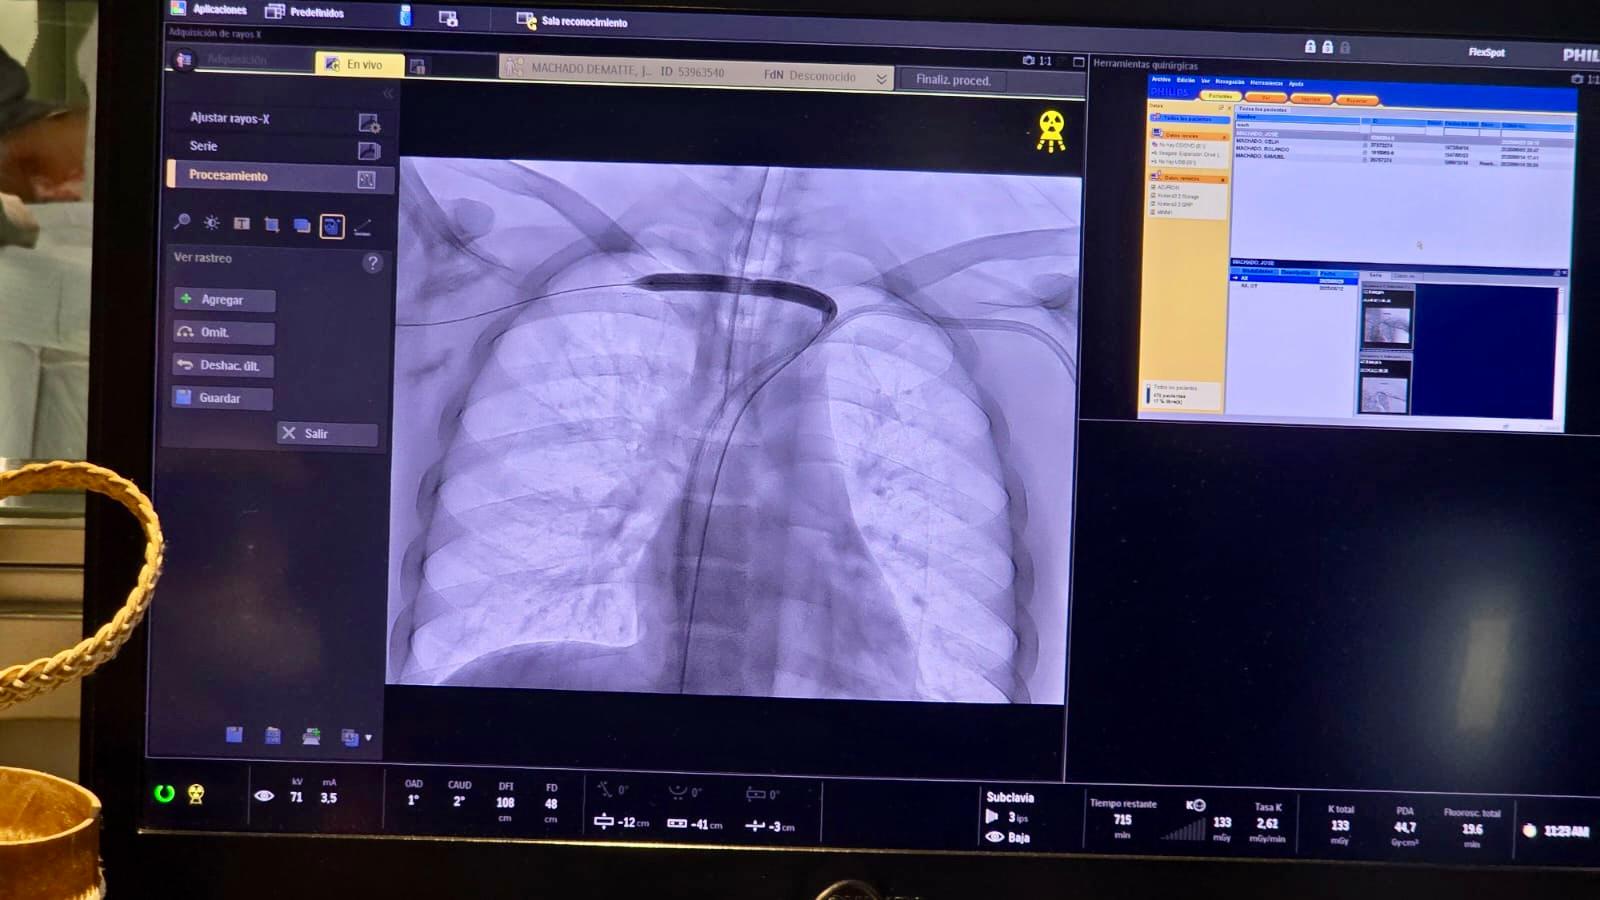

El jueves 11 de setiembre, en el angiógrafo del Hospital Maciel, se realizaron dos intervenciones de gran complejidad para pacientes con insuficiencia renal, sin precedentes en nuestro país.

Un joven de 21 años, de Paso de los Toros, recuperó la funcionalidad de su vena obstruida gracias a la colocación de un stent. Esto permitirá confeccionar la fístula necesaria para que pueda realizarse hemodiálisis, sustituyendo su función renal y mejorando su calidad de vida.

El procedimiento estuvo encabezado por el Dr. Thiago Barroso, cirujano vascular y endovascular procedente de Brasilia, junto al equipo del servicio de Cirugía Vascular del Maciel, liderado por el Dr. Eduardo Ferreira.

Ferreira destacó: “Es un motivo de mucho orgullo que el Hospital Maciel cuente con este angiógrafo y esta sala híbrida, muy moderna, con imágenes de alta calidad y excelente asistencia. Esto es inversión pública que usamos para brindar atención sin cobrar un peso, como debe ser”.

La tecnología del angiógrafo permite realizar procedimientos complejos con seguridad y precisión, beneficiando directamente a los pacientes del sistema público.